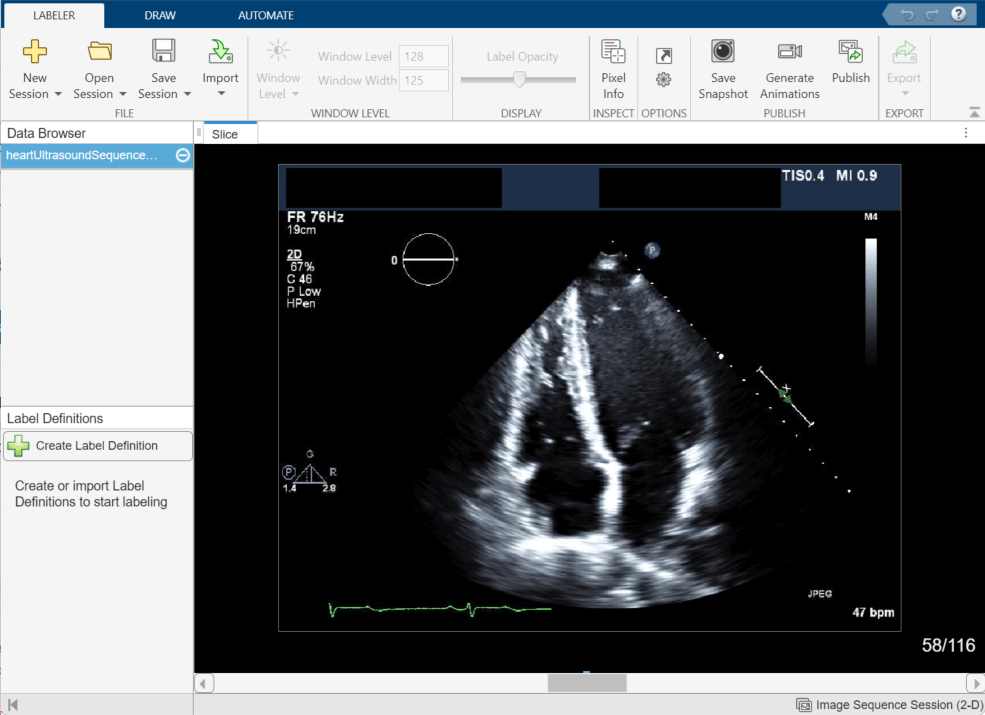

This example shows how to label 2-D image data using the Medical Image Labeler app. The app provides manual, semi-automated, and automated tools for labeling 2-D medical image data. This example labels the left ventricle in an echocardiogram ultrasound image series.

To load an image into the Medical Image Labeler app, on the app toolstrip, click Import. Then, under Data, select From File. Browse to the location of heartUltrasoundSequenceVideo.dcm in the same directory as this example file. For an image session, the imported data file must be a single DICOM file, or a file in a format listed in the imformats file format registry, that contains a 2-D image or a series of 2-D images related by time. You can also import data as a medicalImage object from the workspace.

Explore the Image Series

The Medical Image Labeler app displays the imported image in the Slice pane. By default, the app displays the middle frame in the ultrasound series. You can change the displayed frame by using the scroll bar at the bottom of the Slice pane, or you can click the pane and then press the left and right arrow keys. The app displays the current frame number out of the total number of frames, such as 58/116. You can zoom in on the current frame using the mouse scroll wheel or the zoom controls that appear when you pause on the Slice pane.